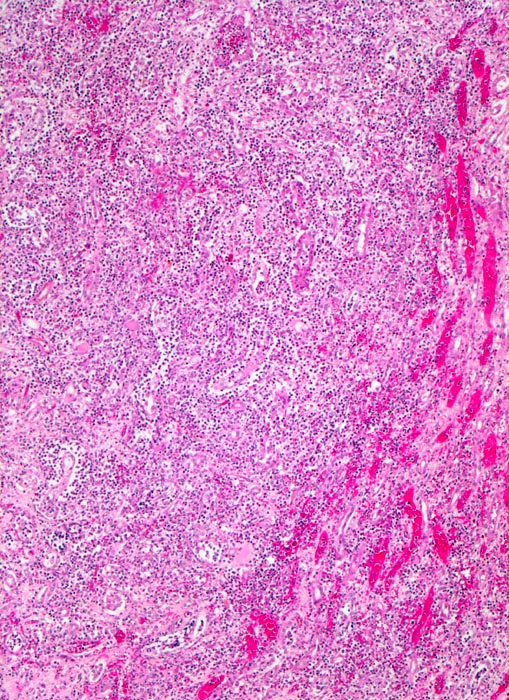

Infektiös eitrige Entzündungen der Niere sind erkennbar an einer Leukozyturie und Granulozytenzylindern. Gelegentlich können eosinophile Granulozyten auftreten.

Bei der Sonderform der xanthogranulomatösen Pyelonephritis ist das Urinsediment oft stark hämorrhagisch und entzündlich verändert und kann Schaumzellen enthalten. Der erste Fall zeigt eine akute eitrige Pyelonephritis. Der zweite Fall eine xanthogranulomatöse Pyelonephritis.